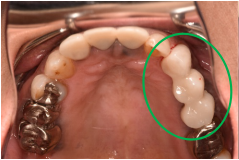

女性Sさん 50代(オールセラミック冠)

主訴

左上の差し歯がとれたままになっている。

治療内容

レントゲンを撮り詳しく診てみると、歯根が破折して保存することができず、抜歯する必要があることがわかりました。抜歯後、オールセラミックブリッジで補綴(欠損した部分を人工物で補う)しました。ブリッジの支台になっている後方の歯は、根尖性歯周炎(根の先端で問題を起こしている)でしたので、根管治療をしています。

所感

抜歯後、欠損部分を補う方法には、1本だけの部分入れ歯、ブリッジ、インプラントの3つの方法があります。この患者さんは、ブリッジを選択されました。メタルフリーの治療を希望されましたので、土台をファイバーコアにし、オールセラミックのブリッジをかぶせました。患者さんは、お口の中の金属を徐々に減らしていきたいということです。体全体の健康のことを考えると正しいことです。

オールセラミック冠(失活歯)1本:¥104,500(税込)

オールセラミック冠(生活歯)1本:¥93,500(税込)

ポンティック1本:¥93,500(税込)

合計:¥291,500(税込)

Before

After